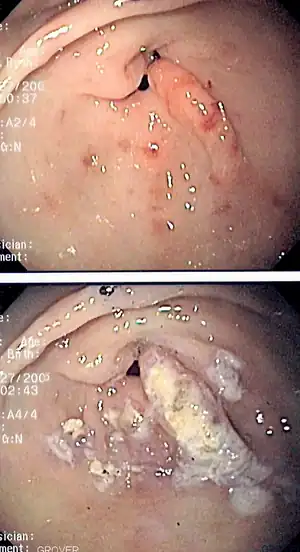

Esophagogastroduodenoscopy images of gastritis with nodularity, erythema and spontaneous oozing, | |